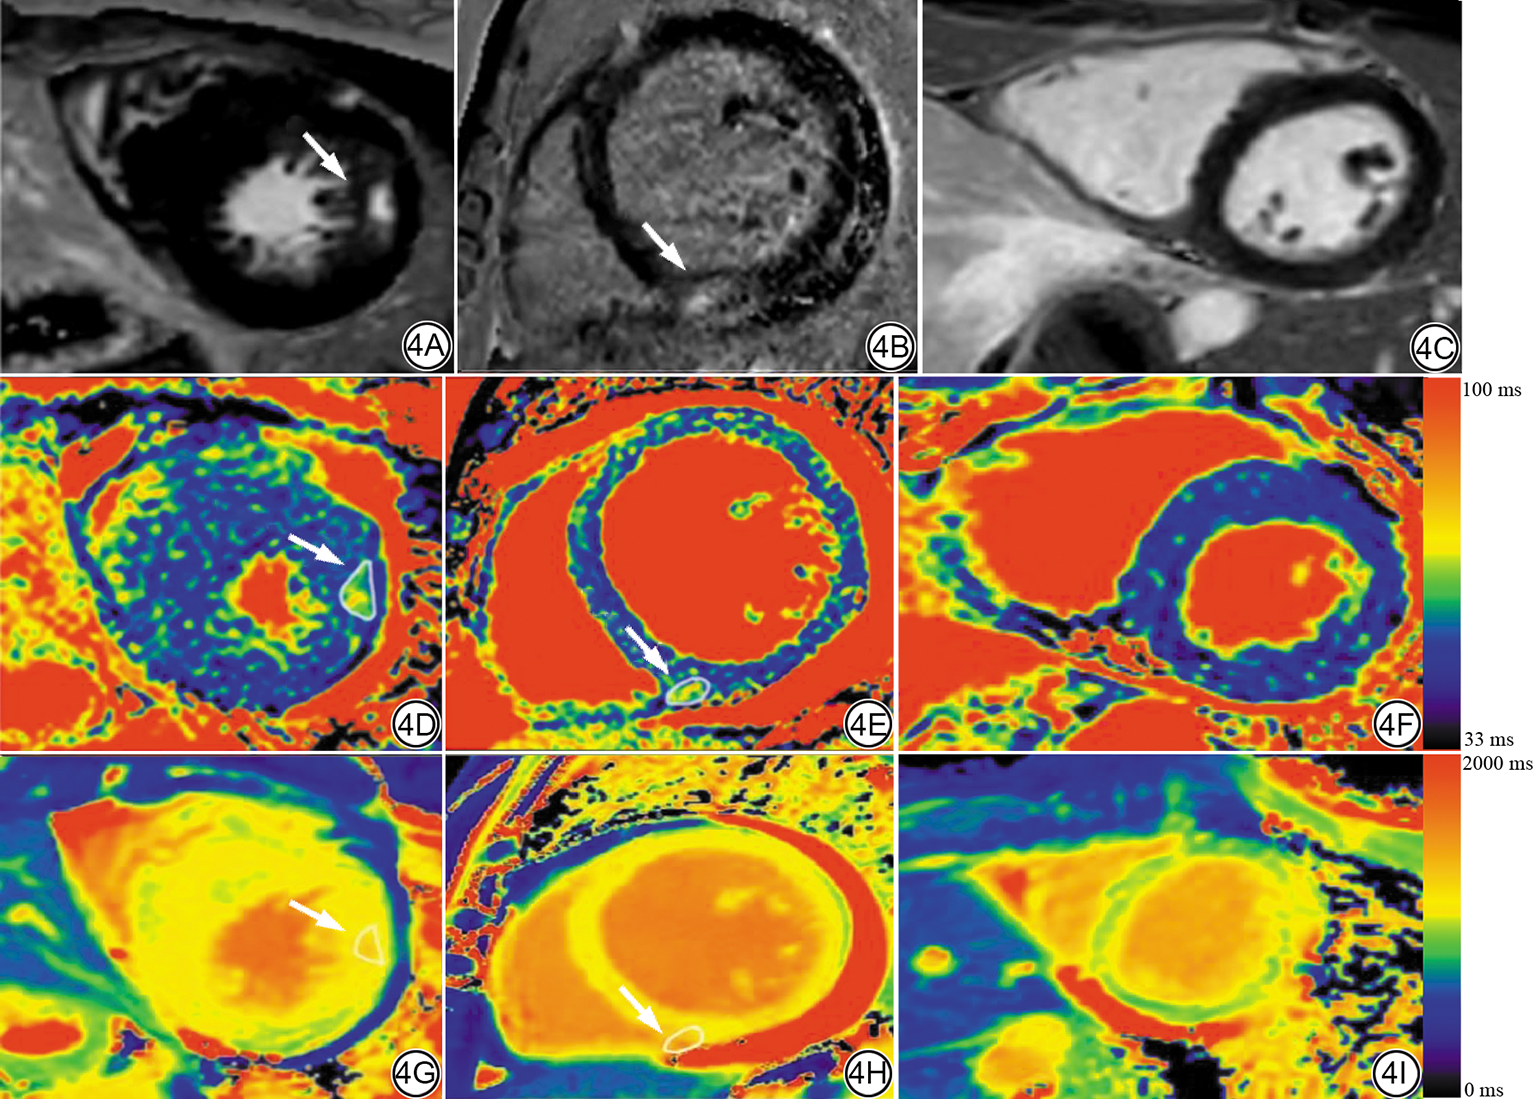

健康志愿者心肌及存在心肌纤维化患者的典型心肌T1ρ mapping图如图4所示。

图4  HCM、DCM和健康志愿者的T1ρ mapping、native T1 mapping和LGE图像。4A~4C均为LGE图像;4D~4F均为T1ρ mapping图像;4G~4I均为native T1 mapping图像;图上的白色箭头所指区域为损伤心肌的ROI。4A、4D、4G为同一个患者图像,女,34岁,最终诊断为HCM;4B、4E、4H为另一个患者图像,男,45岁,最终诊断为DCM;4C、4F、4I为同一个健康志愿者图像,男,18岁。4F和4I旁,从黑色到红色的颜色梯度代表mapping图的弛豫时间,T1ρ mapping为33~100 ms,native T1 mapping为0~2000 ms。HCM:肥厚型心肌病;DCM:扩张型心肌病;LGE:晚期钆增强;ROI:感兴趣区。

Fig. 4  T1ρ mapping, native T1 mapping and LGE images in HCM, DCM, and healthy volunteers. 4A to 4C are LGE images; 4D to 4F are T1ρ mapping images; 4G to 4I are native T1 mapping images. The white arrows indicate the ROIs of injured myocardium. 4A, 4D, 4G: Images from the same patient, female, 34 years old, ultimately diagnosed with HCM. 4B, 4E, 4H: Images from another patient, male, 45 years old, ultimately diagnosed with DCM. 4C, 4F, 4I: Images from the same healthy volunteer, male, 18 years old. The black-to-red color scales adjacent to Figures 4F and 4I represent relaxation times in the mapping images, T1ρ mapping is 33 to 100 ms and native T1 mapping is 0 to 2000 ms. HCM: hypertrophic cardiomyopathy; DCM: dilated cardiomyopathy; LGE: late gadolinium enhancement; ROI: region of interest.